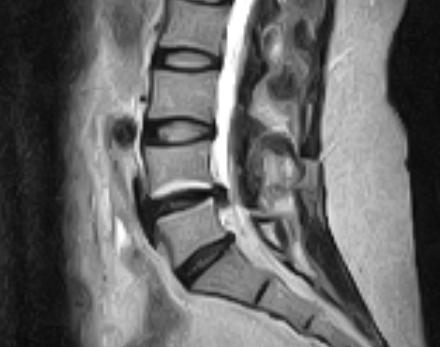

Ще одну складну та цікаву задачу ми виконали разом у КНП ТОКПНЛ ТОР. Ми намагаємося не відмовлятися не від яких випадків та надавати високоякісну та безпечну допомогу своїм пацієнтам.На малюнку справа видно як виглядає кила диску у тубулярний ретрактор під збільшенням у операційному мікроскопі.